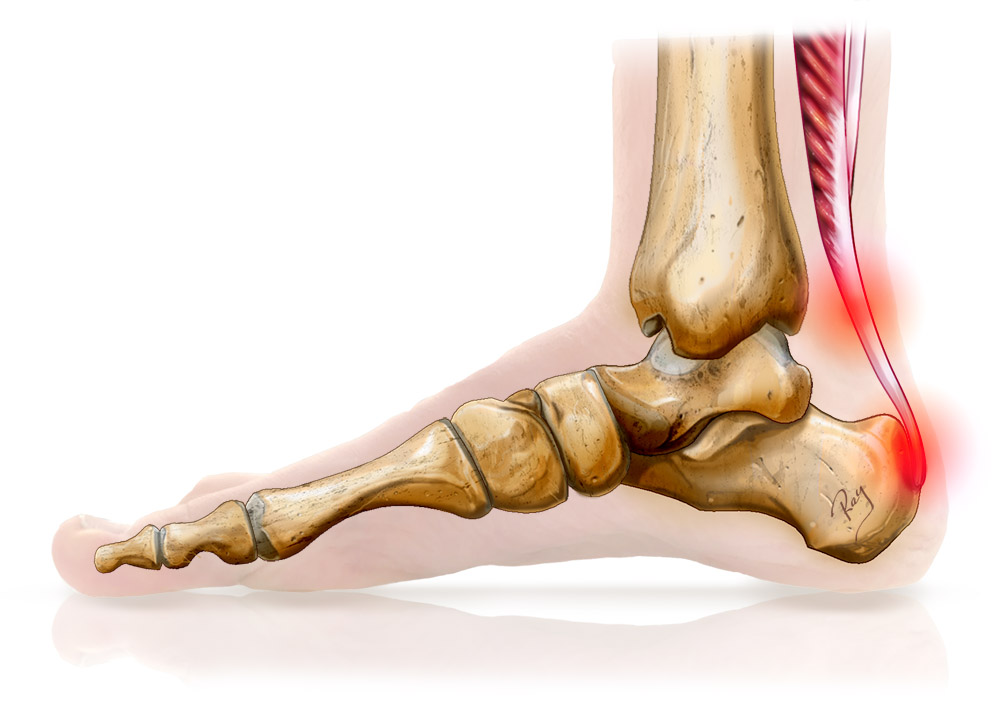

Achilles tendinitis is one of the most common conditions affecting the Achilles tendon, which is the largest tendon in the body. This vital tendon connects the calf muscles to the heel bone, facilitating major movements such as walking, running, and jumping. Nonetheless, too much pressure or repeated stress can cause inflammation, leading to a condition called Achilles tendinitis.

The Achilles tendon is a thick, fibrous tissue that runs from the calf muscles down to the heel bone and allows us to stand on our tiptoes and push off when running. Achilles tendinitis results from the irritation or inflammation of this tendon, which is usually due to overuse.

Symptoms of Achilles Tendinitis

Pain or stiffness at the back of the heel, especially when getting up in the morning.

Swelling along the tendon.

Tenderness or warmth to the touch.